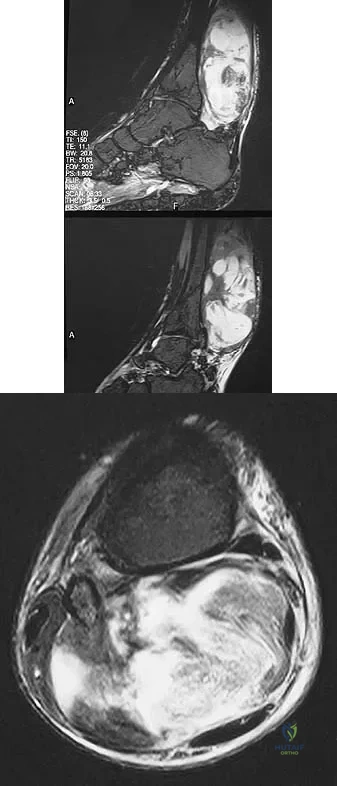

Question 30:

A 42-year-old man reports a 12-month history of a painful fusiform swelling of the Achilles tendon. Physical therapy, heel lifts, and anti-inflammatory drugs have failed to provide relief. MRI scans are shown in Figures 44a and 44b. What is the treatment of choice?

Options:

- Steroid injection

- Debridement and side-to-side repair

- Debridement and flexor hallucis longus tendon transfer

- Brisement

- Continued nonsurgical management with use of a short leg walking cast

Correct Answer: Debridement and flexor hallucis longus tendon transfer

Explanation:

The area of the tendon degeneration is greater than 50% of the width so a supplemental tendon transfer is needed. Debridement and repair alone do not provide adequate strength. Injection risks tendon rupture. Brisement is indicated for peritendinitis, not tendinosis. Nonsurgical management is unlikely to be of benefit after 12 months. Richardson EG (ed): Orthopaedic Knowledge Update: Foot and Ankle 3. Rosemont, IL, American Academy of Orthopaedic Surgeons, 2004, pp 94-95.